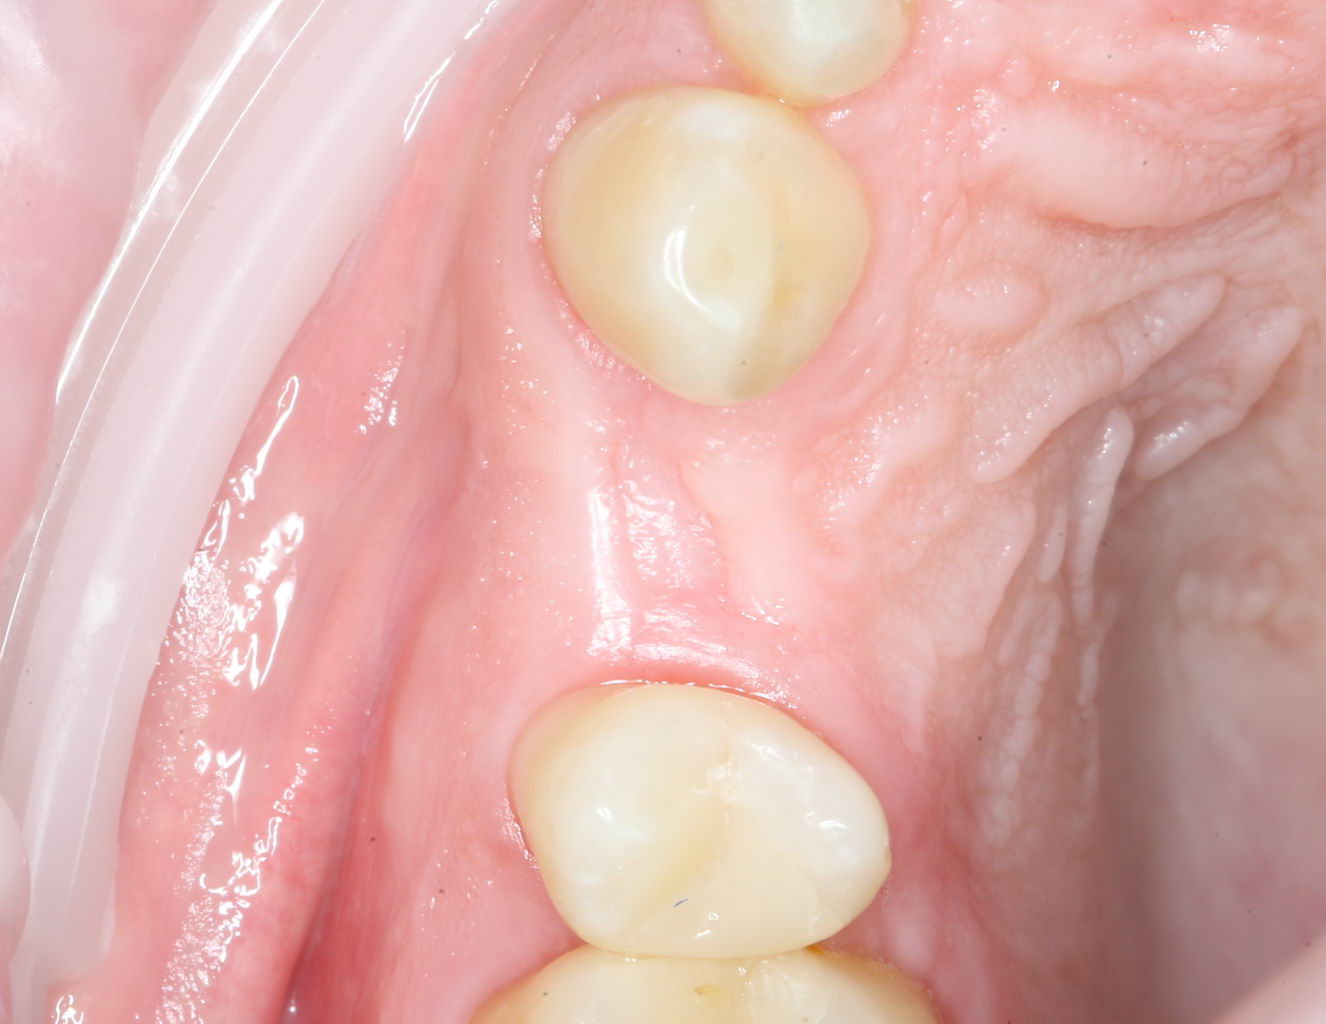

Для окончательного формирования десневого контура, осталось только наложить швы.

Наложение швов.

Помните, в самом начале операции мы планировали наложение швов с учётом будущего вестибулярного смещения лоскута? Так вот, теперь у нас есть возможность не просто сместить, но и зафиксировать вестибулярный лоскут. Делается это, так сказать, с подворотом края снаружи:

Обратите снимание, что альвеолярный отросток в этой области стал более объемным. Этого удалось добиться без всяких остеопластических операций или гингивопластики, путём простого перемещения тканей.

Всё. Операция закончена: